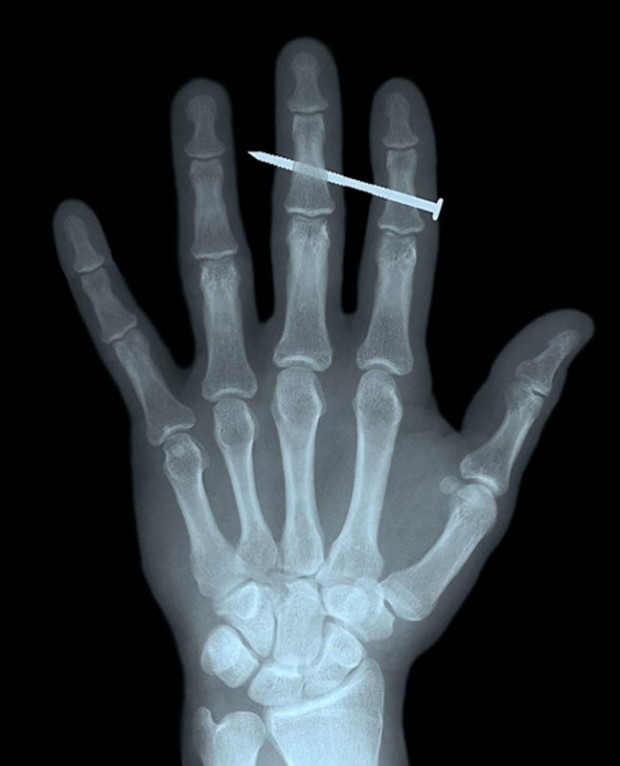

4. Гвоздь в костях указательного и среднего пальцев взрослого мужчины.